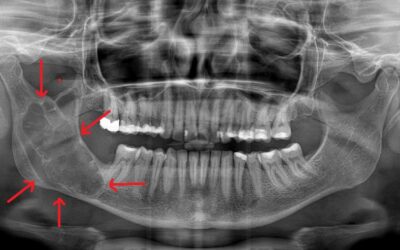

Κύστεις Γνάθων

Ως κύστη ορίζεται μια παθολογική κοιλότητα που επαλείφεται από επιθήλιο. Οι κοιλότητες που δεν επαλείφονται από επιθήλιο χαρακτηρίζονται ως ψευδοκύστεις. Οι κύστεις που εντοπίζονται στην άνω και την κάτω γνάθο και τις περιοχές γύρω από τη στοματική κοιλότητα...